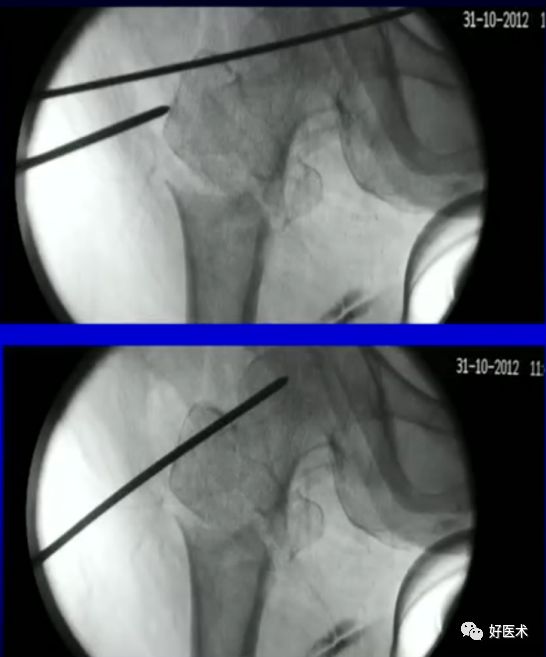

1.撬拨技术

用克氏针或斯氏针对移位的骨折块进行撬拨复位。

病例一:女 94岁

体表定位与撬棒置顶

撬棒置顶后内收情况

正位进针位置调整情况

主钉插入后的导针正侧位